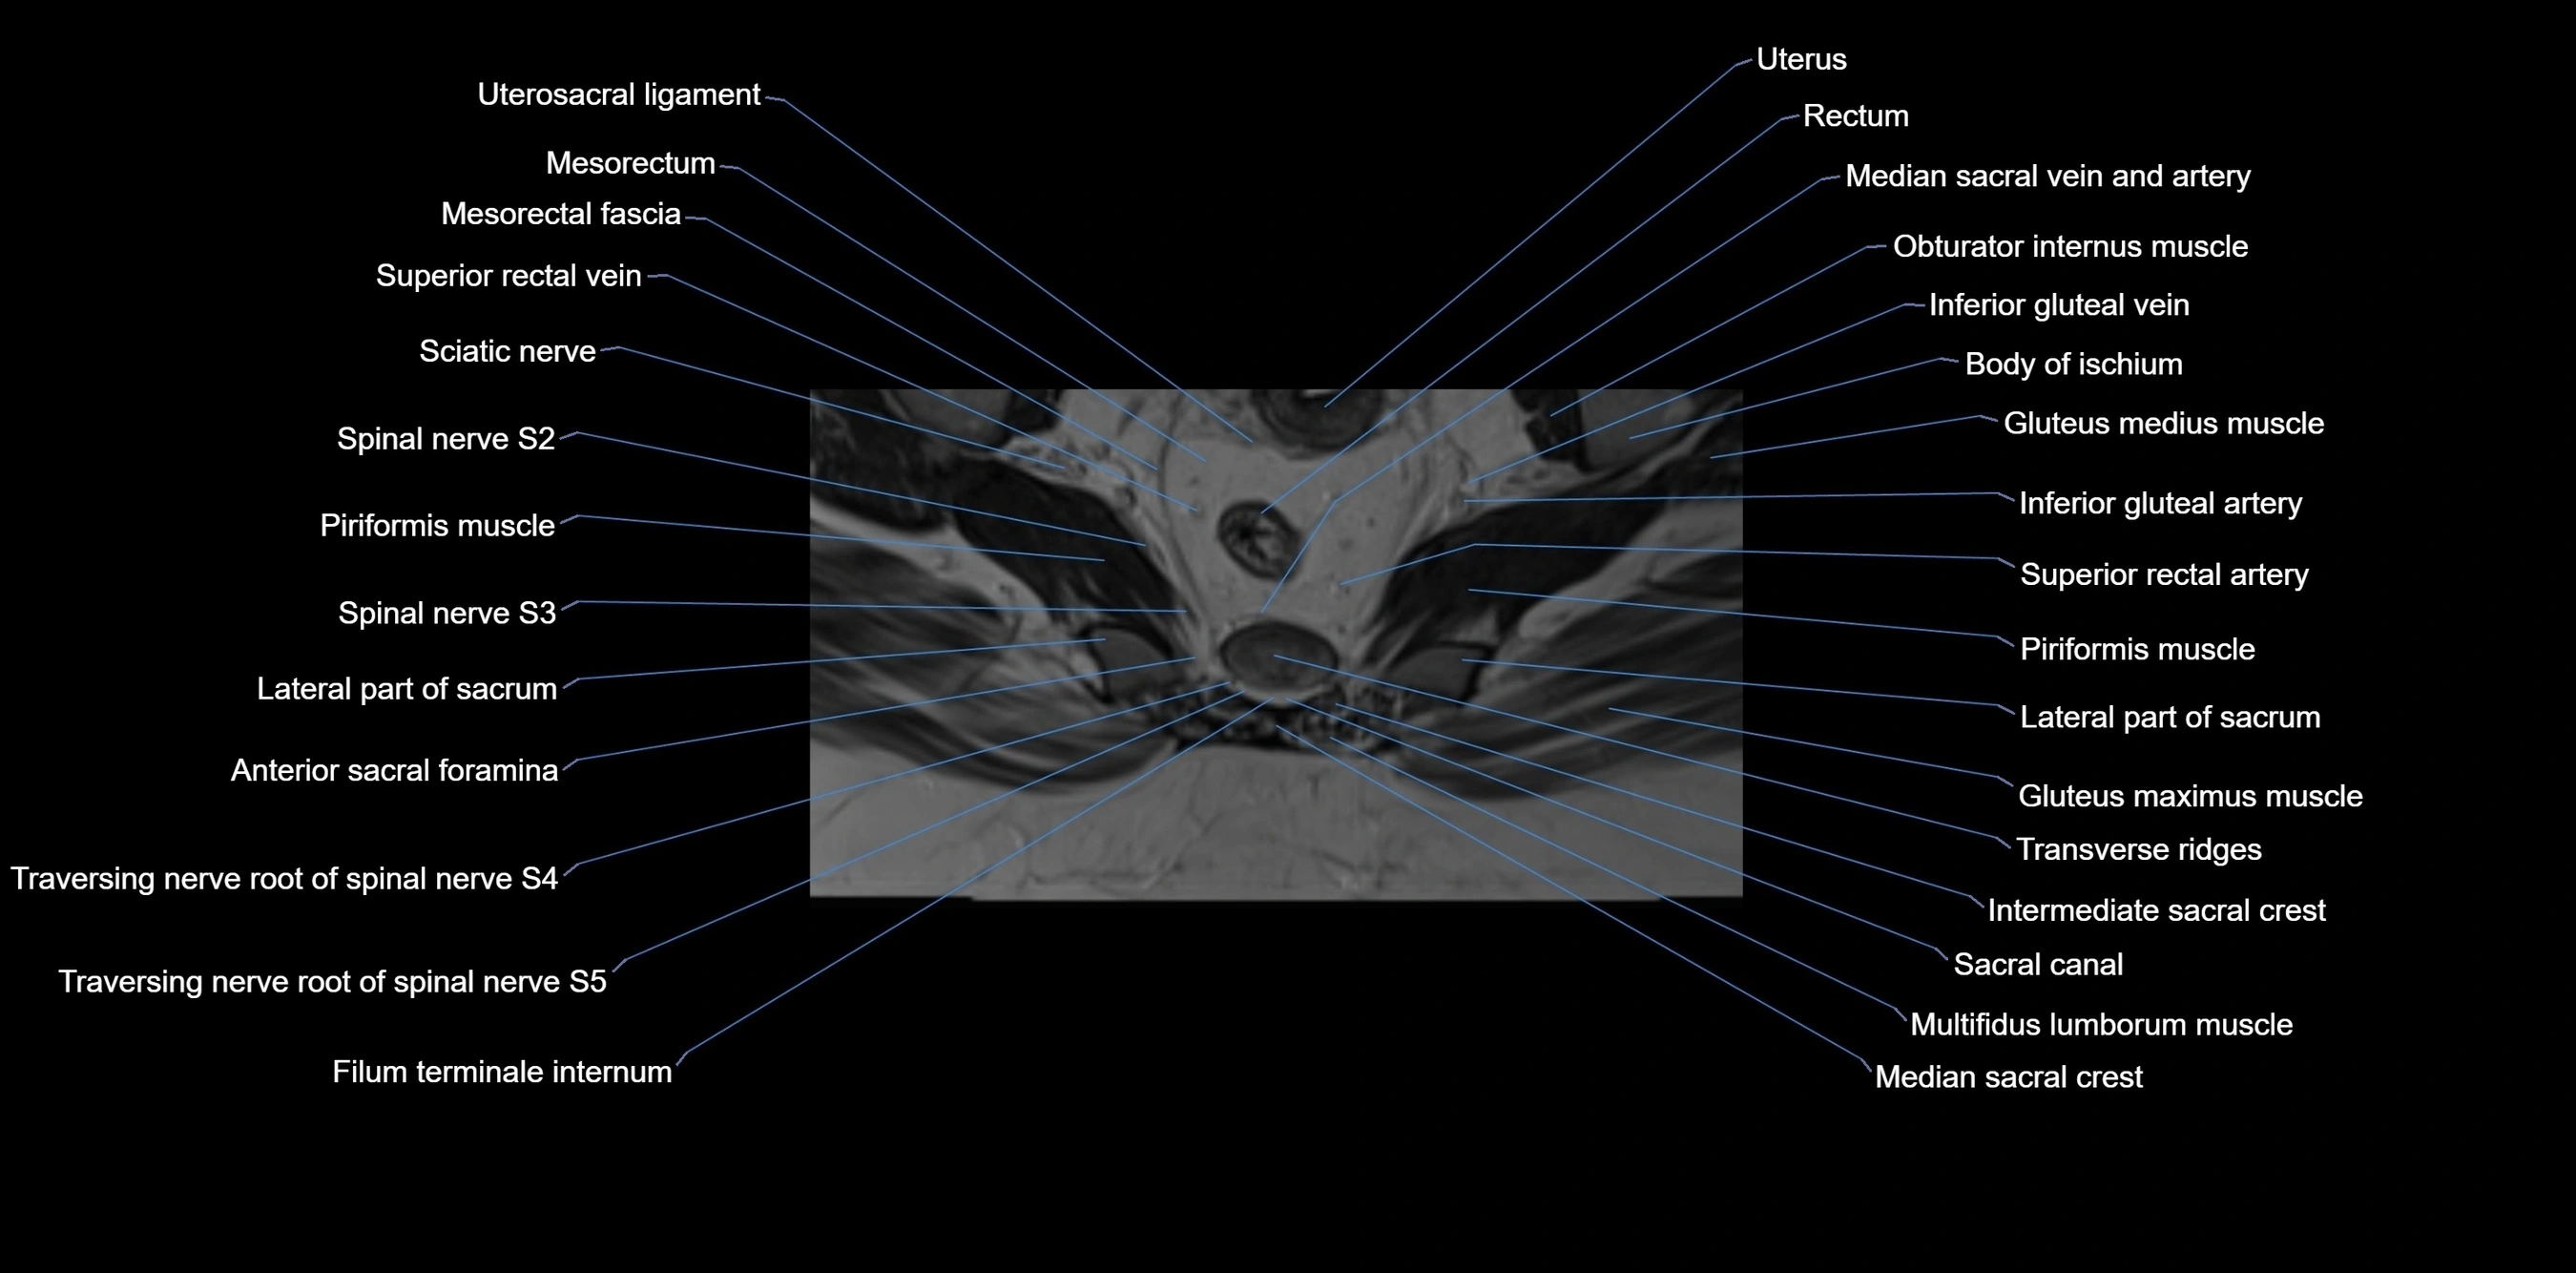

MRI image

image